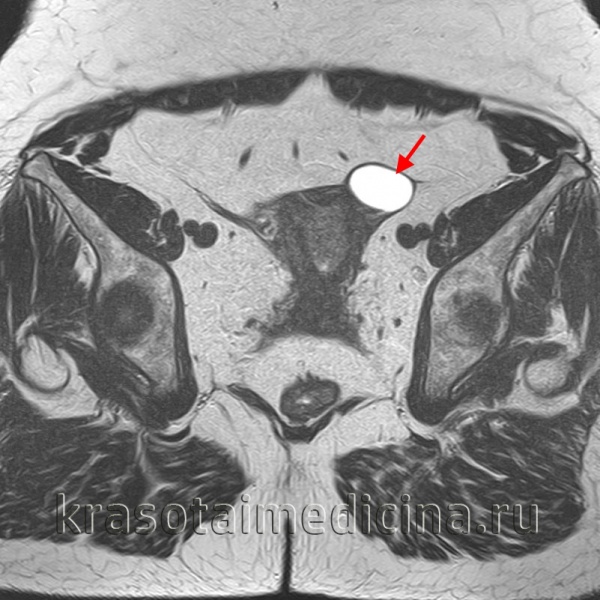

• магнитный или компьютерный резонанс (КТ или МРТ), предоставляющий информацию о местонахождении, размере, структуре, содержимом кисты яичника и его взаимосвязи с нижележащими органами.

МРТ таза. Однокамерная киста левого яичника.